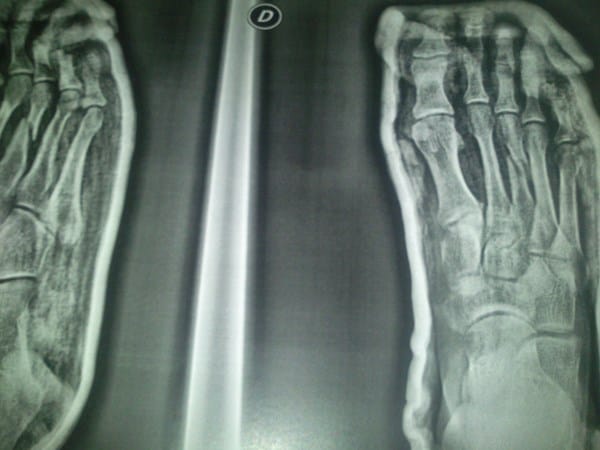

Fractura del 3º Metatarsiano pie dcho

Hace 1 mes me partí el 3 metatarsiano en un partido de liga, fue en un balón dividido y creo que me dio un punterazo. En ese mismo momento pido el cambio y me trasladan a urgencias, donde me diagnostican la fractura y me colocan una escayola, solo por la parte de abajo y atrás del gemelo, no por toda la pierna. Me dicen que no hay que operar si en 3 semanas no se mueve, pasan las 3 semanas, pero el hueso sigue igual exactamente, incluso yo diría peor que al principio. Fui ayer otra vez y me dijo que siguiera un mes mas con escayola como mínimo, pero pido segunda opinión y algunos fisios me comentan que esta muy desplazado y me voy a tener que operar, que me busque un traumatólogo cirujano. Aquí os adjunto la rx ultima

¿Creen qué iré a quirófano? ¿Debería? ¿Seria lo mejor?